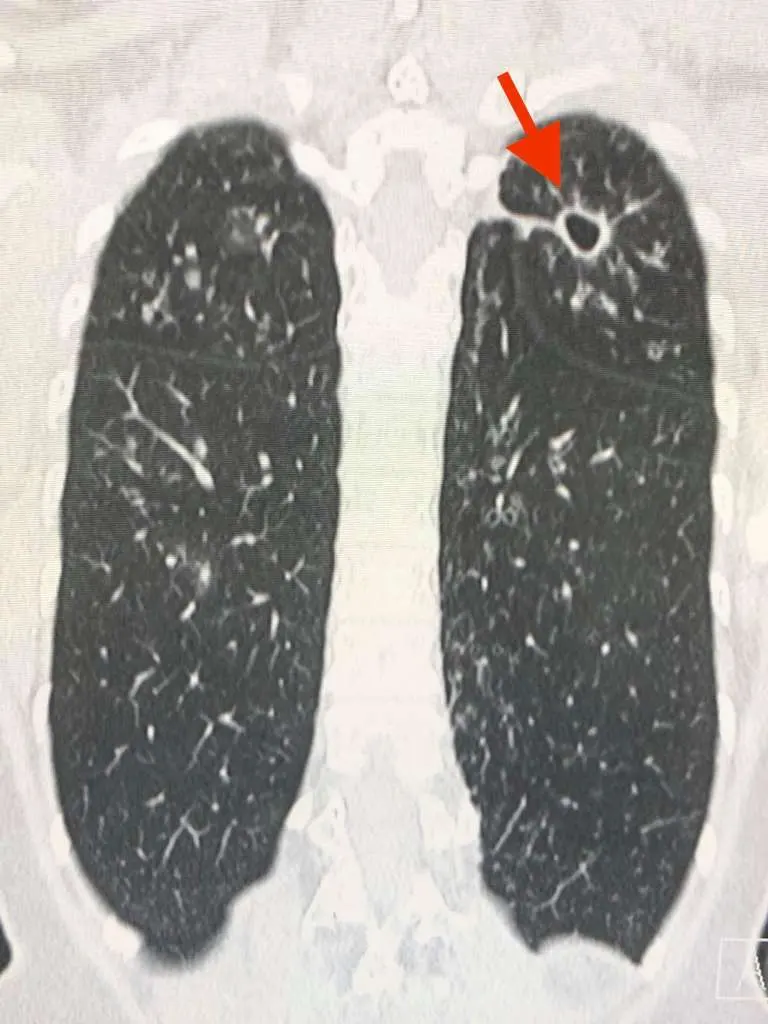

สาเหตุที่สำคัญน่าจะเป็นจากเชื้อไวรัสโควิด-19 ในประเทศอิตาลีเป็นเชื้อสายพันธุ์ที่ดุร้ายกว่าประเทศอื่นในเอเชีย สามารถเพิ่มจำนวนในปอดได้รวดเร็ว ทำให้แพร่กระจายเชื้อให้ผู้อื่นมากขึ้น และเชื้อนี้เล่นงานปอดอย่างหนัก ทำให้ปอดอักเสบอย่างรุนแรง ระบบหายใจล้มเหลว อัตราการเสียชีวิตจึงสูงมาก

ประเทศไทยกำลังมีเชื้อโควิดที่ดุร้ายจากประเทศอิตาลีแพร่ระบาด ยอดผู้ป่วยติดเชื้อรายใหม่ (ดูรูป) และผู้เสียชีวิตจากปอดอักเสบกำลังจะเพิ่มขึ้นอย่างรวดเร็ว สำหรับผู้ป่วยที่ติดเชื้อโควิดรายใหม่ที่เกี่ยวข้องกับสนามมวย แพทย์คงต้องให้ยาต้านไวรัสตัวใหม่จากประเทศญี่ปุ่น ชื่อยา Avigan คือฟาวิพิราเวียร์ (Favipiravir) และยาอื่นๆเช่น hydroxychloroquine เพราะผู้ป่วยรายใหม่กลุ่มนี้จะมีปอดอักเสบมากขึ้น ถ้าไม่ให้ มีโอกาสปอดล้มเหลวสูง